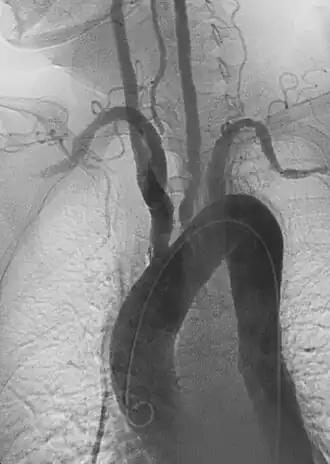

Эндоваскулярное восстановление аневризмы: установка эндоваскулярного стент-графта через аневризму для предотвращения расширения или прогрессирования дефектного сосуда.[6]

Расслоение означает разрыв внутреннего слоя стенки артерии. Кровь закачивается в этот дефект и прокладывает себе путь между слоями стенки артерии, создавая ложный канал, отдельный от истинного артериального просвета. Расслоения могут возникнуть вследствие травмы, спонтанно из-за повышенного артериального давления и врожденного сосудистого заболевания, а в некоторых случаях — как осложнение ранее проведенного хирургического или эндоваскулярного лечения.

При расширении артериальной диссекции может быть ограничен нормальный кровоток через пораженную артерию или потенциально заблокировано начало ответвления сосуда — в любом случае это может нарушить дистальную перфузию. В остром состоянии и с симптомами это неотложное состояние, требующее немедленного лечения.

Однако по мере совершенствования медицинской визуализации были обнаружены и хронические бессимптомные расслоения, и в некоторых случаях их можно безопасно лечить с помощью контроля артериального давления, последующей визуализации и надлежащего консультирования по признакам потенциальной ишемии.

Расслоения могут возникнуть в любой артерии и называются по названию сосуда, из которого они происходят. Расслоения аорты можно дополнительно классифицировать и лечить в зависимости от того, затрагивает ли они грудную аорту, брюшную аорту или обе. Классическая боль, связанная с острым расслоением аорты, описывается как «разрывающая» или «разрывающая» и может отдавать в спину пациента. Острое расслоение аорты может быть трудно диагностируемым, но встречается чаще, чем разрыв аневризмы аорты.

Расслоения грудной аорты далее характеризуются с помощью Стэнфордской классификации.[38] Расслоения типа А затрагивают корень и восходящую часть аорты. Они требуют незамедлительного лечения, которое в настоящее время носит в основном хирургический характер. Расслоения типа B начинаются в дистальной части дуги аорты за пределами места отхождения левой подключичной артерии и часто могут быть устранены с помощью обезболивающих препаратов и контроля артериального давления. Если расслоение аорты типа B приводит к ухудшению кровообращения в кишечнике, почках или ногах, часто требуется срочное эндоваскулярное восстановление с использованием эндопротезов и/или фенестраций. Если расслоение аорты типа B разорвалось или имеются признаки, указывающие на приближающийся разрыв, их также срочно лечат.

Лечение расслоения зависит от нескольких факторов, включая локализацию, степень, длительность развития (острое или хроническое) и ограничение перфузии. Хирургические подходы к расслоению аорты могут включать реконструкцию аорты, хирургическое шунтирование и хирургическую фенестрацию. Как и при других артериальных заболеваниях, эндоваскулярные подходы к диссекции, такие как стентирование[40] и чрескожная фенестрация[41] могут использоваться как в качестве основного метода, так и в сочетании с хирургическим вмешательством в зависимости от сложности диссекции.